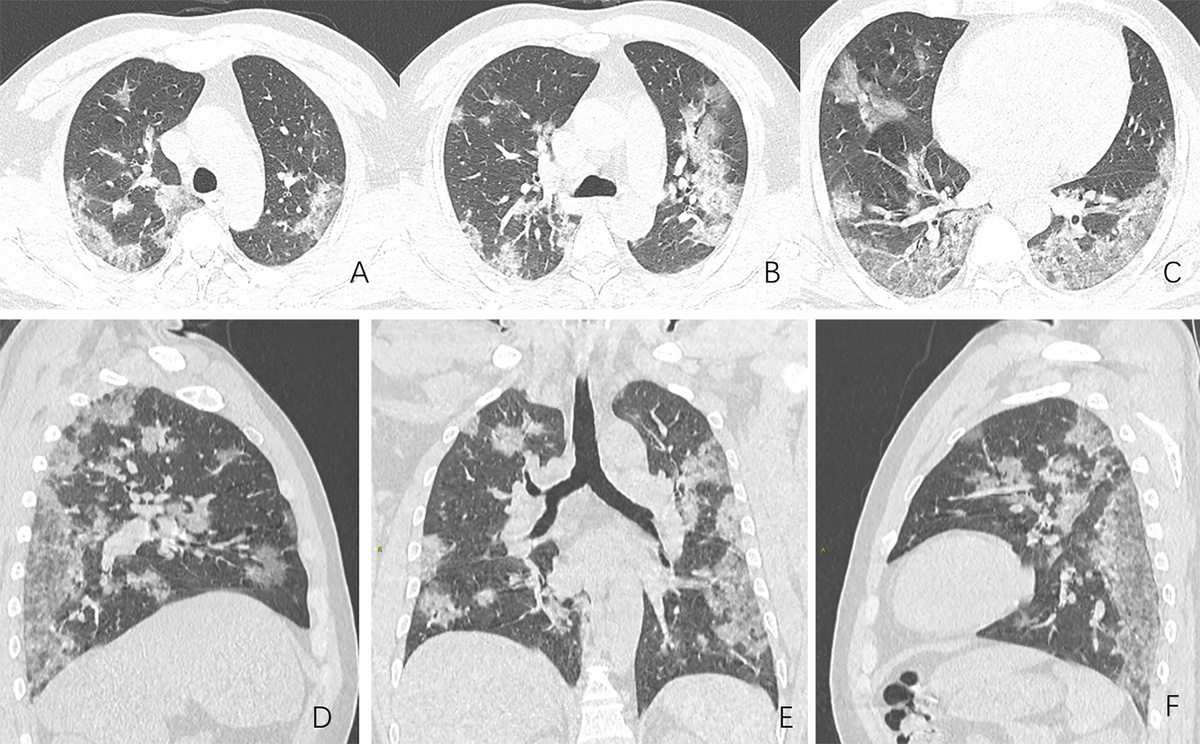

Поэтому повезли на КТ, где оказалось поражено 52 процента легкого. Стали возить по больницам. Везде отказ. К ночи пристроили в только что открывшуюся.